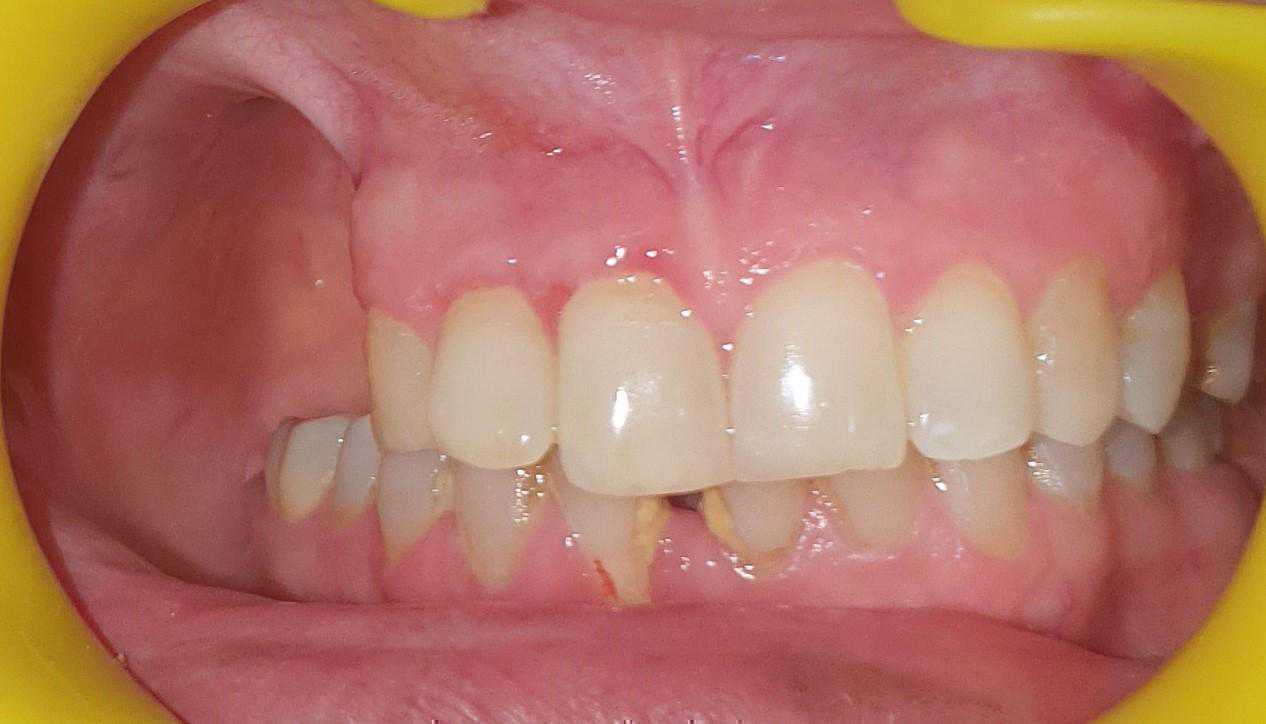

https://demo.discussdentistry.com/forums/topic/post-mucormycosis-avascular-necrosis-of-maxilla-rehabilitation-with-zygomatic/#post-24499 <![CDATA[Post Mucormycosis Avascular necrosis of maxilla, rehabilitation with Zygomatic]]> https://demo.discussdentistry.com/forums/topic/post-mucormycosis-avascular-necrosis-of-maxilla-rehabilitation-with-zygomatic/#post-24499 Thu, 25 Aug 2022 12:14:40 +0000 Sankalp Mittal

• 20210604_101325 (2)20210604_101317 (2)20210604_103315 (2)20210604_102857 (2)20210604_104202 (2)20210604_104853 (2)20210824_105656 (2)20210824_112353 (2)20210824_114957 (2)20210824_131302 (2)20210826_100648 (2)20210826_100749 (2)20210826_100919 (2)20210914_183943 (2)20211001_17535220211012_18543620211012_192043 (2)20211012_185627 (2)20211012_195430 (3)20211027_193725 (2)20211027_200729 (2)20211027_200919